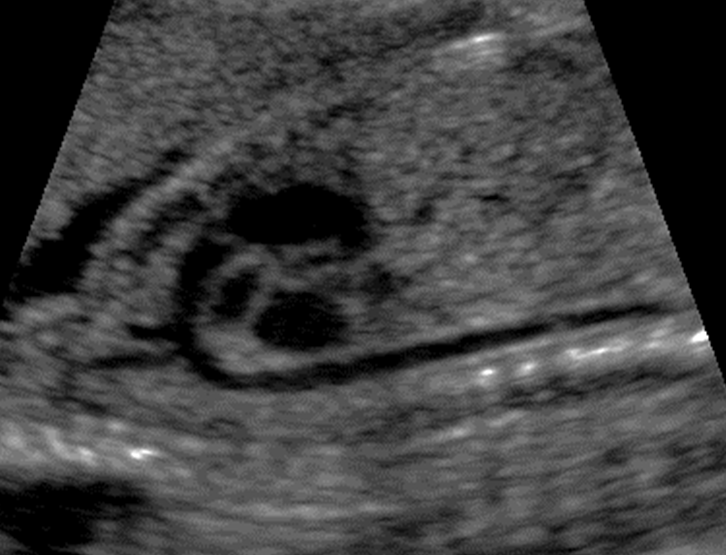

What view is this?

Crisscross view